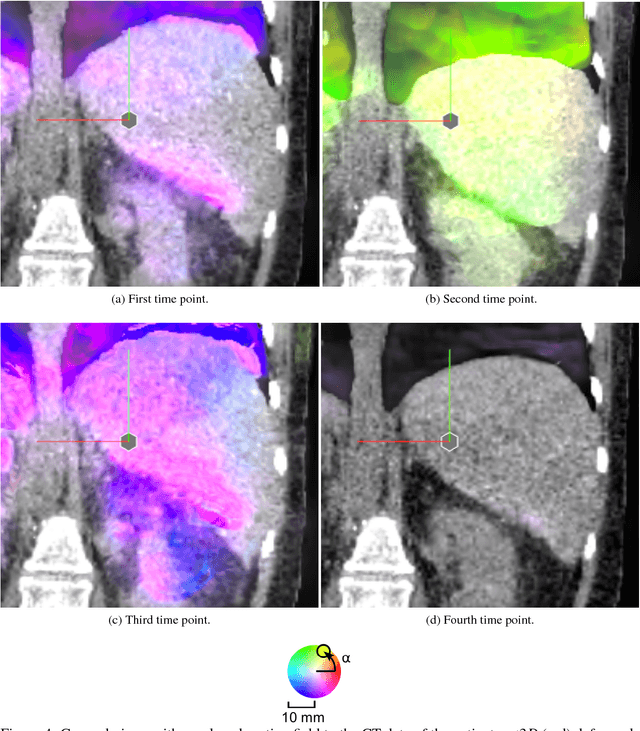

Abstract:Virtual reality (VR) training simulators of liver needle insertion in the hepatic area of breathing virtual patients currently need 4D data acquisitions as a prerequisite. Here, first a population-based breathing virtual patient 4D atlas can be built and second the requirement of a dose-relevant or expensive acquisition of a 4D data set for a new static 3D patient can be mitigated by warping the mean atlas motion. The breakthrough contribution of this work is the construction and reuse of population-based learned 4D motion models.

Abstract:Current virtual reality (VR) training simulators of liver punctures often rely on static 3D patient data and use an unrealistic (sinusoidal) periodic animation of the respiratory movement. Existing methods for the animation of breathing motion support simple mathematical or patient-specific, estimated breathing models. However with personalized breathing models for each new patient, a heavily dose relevant or expensive 4D data acquisition is mandatory for keyframe-based motion modeling. Given the reference 4D data, first a model building stage using linear regression motion field modeling takes place. Then the methodology shown here allows the transfer of existing reference respiratory motion models of a 4D reference patient to a new static 3D patient. This goal is achieved by using non-linear inter-patient registration to warp one personalized 4D motion field model to new 3D patient data. This cost- and dose-saving new method is shown here visually in a qualitative proof-of-concept study.